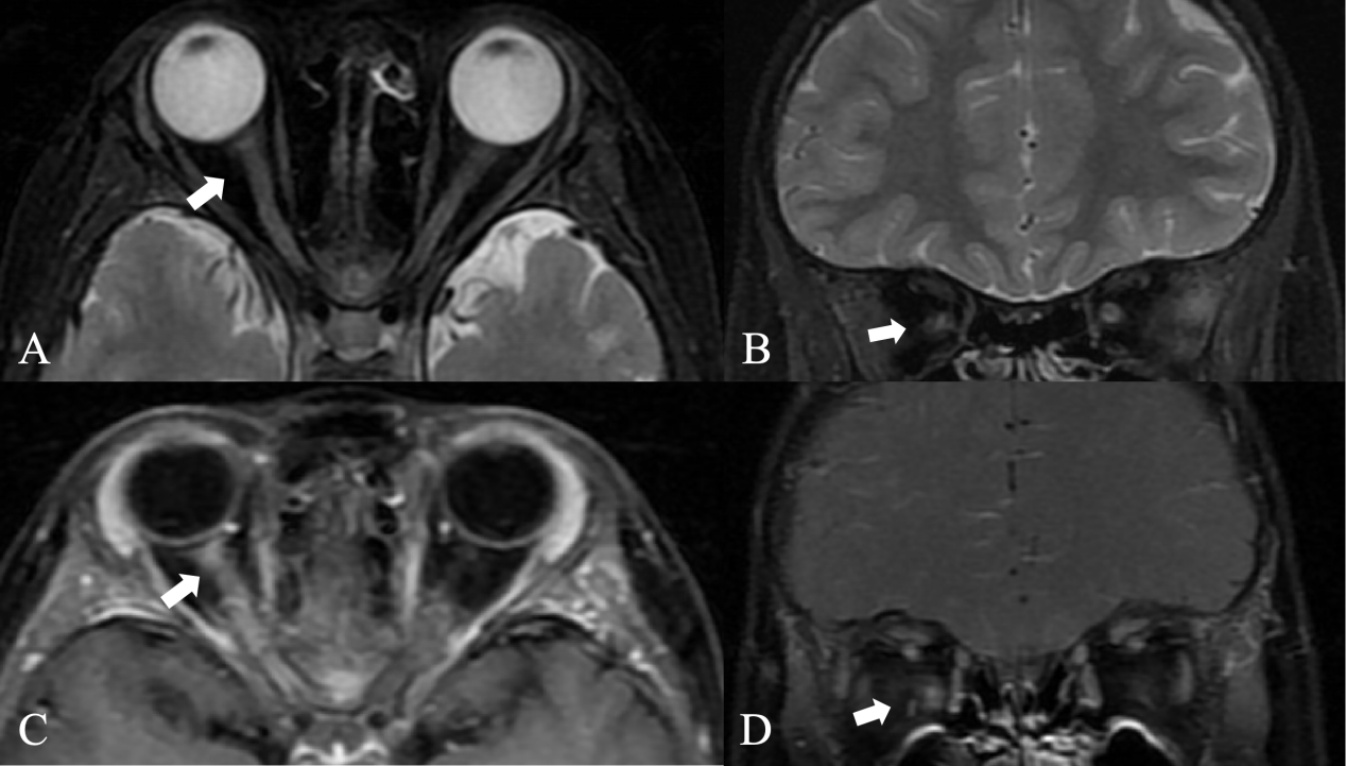

脊髓炎患者的MRI通常累及三个及以上的椎体,表现为纵向广泛的长节段横贯性脊髓炎(Longitudinally Extensive Transverse Myelitis, LETM)。MOG-IgG儿童的广泛脊柱受累主要作为(Acute Disseminated Encephalomyelitis, ADEM)发作的一部分或仅作为LETM发生[23]。在66%~75%的MOG-IgG患者中,脊髓T2高信号病变在轴位成像上位于中心。并可局限于灰质(如30%~50%的患者所见),产生H征[17]-[19] (图2)。在脊髓炎中,50%的患者可出现强化特征,但具体强化特点并未描述,马尾强化已被报道[17] [18] [24] [25],在MOGAD儿童中软脑膜强化约占53%,可同时患有LETM,并且这些软脑膜强化部位主要集中在脊髓病变附近[23]。有研究发现,34%的MOGAD患儿可出现脊神经根强化[24] [25]。软脑膜和神经根强化可能源于局部软脑膜或神经根鞘的炎症浸润,或许与其周围神经系统中MOG的表达有关[26]

脊髓T2矢状位上显示纵向广泛长节段性病变(A,箭头),轴位T2高信号上局限于灰质,形成特征性H征(B, C),T1增强后出现了相应的强化(D,E,箭头)。注:图片引自Zhang等(2024) [38]

Figure 2. MRI findings in MOG myelitis

2. MOG脊髓炎在MRI上的表现

MOG脑炎在MRI上增强很常见,约占73%,通常是非特异性的,轮廓不清,呈斑片状外观,可有多灶性结节状强化,皮质强化,并且很少持续超过3个月,与AQP-4阳性NMOSD和MS的相比,软脑膜强化约占33% (图3)。由于皮层本身存在MOG抗原的分布[32],皮层出现强化可能是由于MOG抗体与抗原结合,造成了炎症细胞的浸润[33],增强后由于血脑屏障破坏,进而出现相应强化。Elsbernd等人认为,MOGAD软脑膜增强可能与头痛、发热、癫痫发作等有关,其强化更倾向于MOGAD [34]。Cobo-Calvo等人发现,颅神经受累可与MOG抗体疾病患者共存,T1WI增强后显示其根部水平强化,其潜在的病理生理学难以捉摸,他们认为这种颅神经参与可能是由于脑桥病变的炎症下游的结果[35]。Li等人发现,有患者在丘脑、内囊后肢区域表现为T2WI明显的不均匀高信号,边界不清,类似一个大的水肿性病变,在T1WI增强上表现为蓬松的“火焰样”或绒毛样外观。病理活检为肿胀性脱髓鞘病变。也有部分患者出现大脑皮层下白质中脑回或带状增强[30]

右侧颞叶皮层T2 Flair信号稍高(A,箭头),T1增强后软脑膜强化(B,箭头),双侧桥臂及右侧小脑半球多发T2 Flair稍高信号影(C,箭头),增强后出现多灶性结节状强化(D,箭头)。

Figure 3. Enhancement of MOG-related brain lesions

3. MOG脑部病变的强化